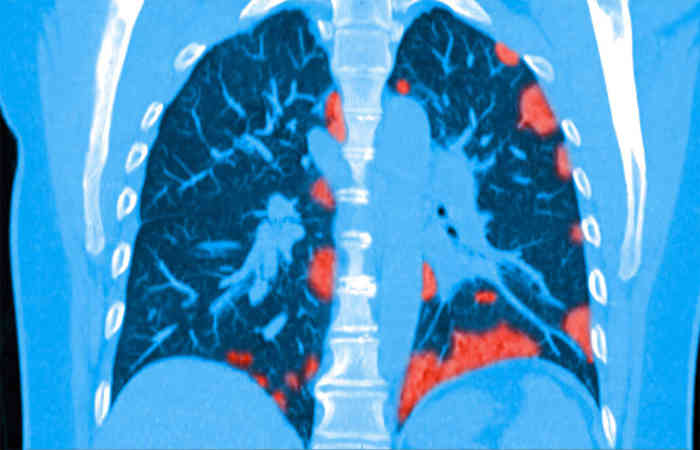

दुनियाभर में कोरोना वायरस से संक्रमित रोगियों की संख्या बढ़ रही है। बढ़ती मौत का आंकड़ा चिंताजनक है। इस सब के बीच में घातक कोरोना वायरस से जुड़ी एक और चौंकाने वाली जानकारी आई। संयुक्त राज्य अमेरिका में कोरोना वायरस पर शोध करने वाले वैज्ञानिकों की एक टीम ने पता लगाया है कि कोरोना वायरस SARS CoV-2 उन रोगियों में 90 दिनों तक रहता है जो बहुत गंभीर स्थिति के बाद ठीक हो जाते हैं। कोरोना से उबरने वाले मरीजों को घर से बाहर नहीं जाना चाहिए और कम लोगों से मिलना चाहिए।

वैज्ञानिकों ने पता लगाया है कि जो लोग कोरोना से बरामद हुए हैं वे 90 दिनों तक किसी को भी संक्रमित कर सकते हैं। कोरोना से उबरने के बाद घर लौटे मरीजों को घर पर रहने की सलाह दी जाती है। विशेष रूप से, कोरोना से संक्रमित रोगियों की संख्या 65 लाख के आंकड़े को पार कर गई है। जबकि एक लाख से ज्यादा लोग मारे गए हैं।

अमेरिका के अटलांटा में रोग नियंत्रण और रोकथाम केंद्र द्वारा एकत्र आंकड़ों के अनुसार, एक गंभीर कोरोनरी हृदय रोग से गुजरने वाले रोगी में 90 दिनों तक संक्रमण फैलने की संभावना होती है। दूसरी ओर, कोरोना उन रोगियों में भी 10 दिनों तक मौजूद होता है, जिनका हल्का कोरोनरी प्रभाव हल्का होता है। कमजोर प्रतिरक्षा प्रणाली वाले रोगी के संपर्क में आने वाले लोगों के संक्रमित होने की संभावना अधिक होती है।